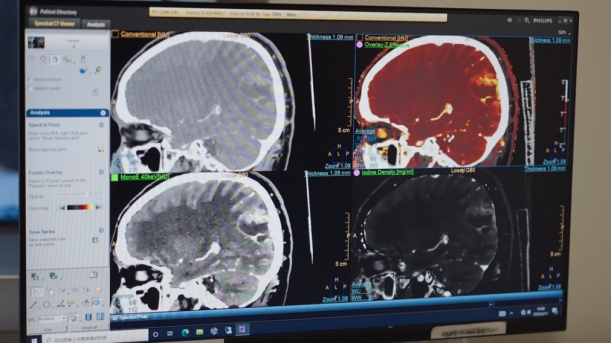

“比如我们现在应用的能量CT成像技术,它可以利用物质在不同能量射线作用下的衰减特性不同的原理来获取更多物质的特性信息,有助于更准确地发现隐匿性病变、鉴别不同组织的性质、定量组织间灌注的差异以及评估疾病的疗效等,在罕见病诊断中具有独特的优势。”冯逢介绍。

近年来,随着CT技术的发展与完善,能量CT在临床应用中的表现愈加突出。协和医院放射科将能量CT成像技术应用于罕见病诊断,找到了罕见病影像诊断的“精准之钥”。谈及能量CT,冯逢具体总结了以下几点优势:

其一,能量CT具有高灵敏度的物质鉴别能力,可以实现精准的物质分离,区分出传统CT难以辨别的组织或特殊病理成分,检测出微小病变,对罕见病如胃肠胰神经内分泌瘤、黑色素瘤等的影像评估有显著优势;

其二,在罕见病能量成像中,能量CT不再依靠单一CT值为影像诊断依据,而是利用多个参数相互验证,提供更精准的诊断,对于罕见病的临床诊疗提供很有价值的信息;

其三,很多全身性罕见病会累及血管,基于能量CT的黑血成像对于血管壁受累显示清晰,可以在后续血管疾病诊疗中推广,通过能量成像达到满意诊断效果,从而使罕见病患者中血管受累的患者受益;

其四,能量CT成像对于罕见病患者预后评估也提供更多信息,比如放化疗的肿瘤患者,不单单依靠肿瘤大小、密度去判断疗效,而定量整个肿瘤中不同成分的摄碘量、有效原子序数值等体积占比的变化,这提示了整个肿瘤的治疗前后的组织学变化。